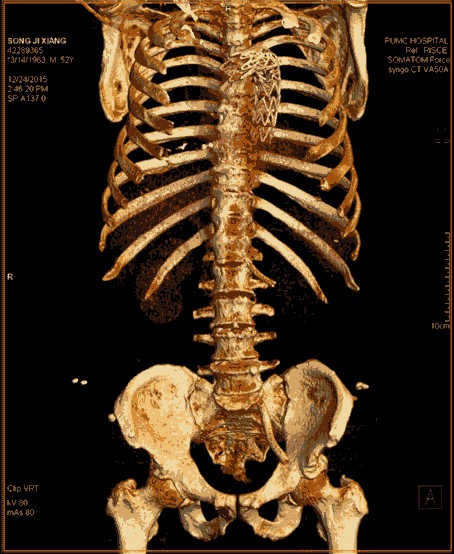

近日,代表當前CT最高水平的西門子SOMATOM Force開源CT在滕州市中心人民醫(yī)院正式啟用。Force CT采用全球獨創(chuàng)的雙球管、雙探測器結(jié)構(gòu),臨床應(yīng)用領(lǐng)域廣泛,在全身各部位的無創(chuàng)成像方面開創(chuàng)了高端CT應(yīng)用的新紀元,尤其在冠心病冠脈成像方面有無可比擬的優(yōu)勢,其操作便捷、安全無創(chuàng)和綠色環(huán)保引領(lǐng)著業(yè)內(nèi)的標桿和典范,被稱為“窺心神器”。

SOMATOM Force是全新的第三代雙源CT,革新了球管、高壓發(fā)生器、探測器、數(shù)據(jù)采集系統(tǒng)、重建系統(tǒng)等一系列影像鏈,定義了一個無與倫比的 CT 性能等級,開辟了全新的CT影像時代,可以做到更快、更寬、更能、更低。